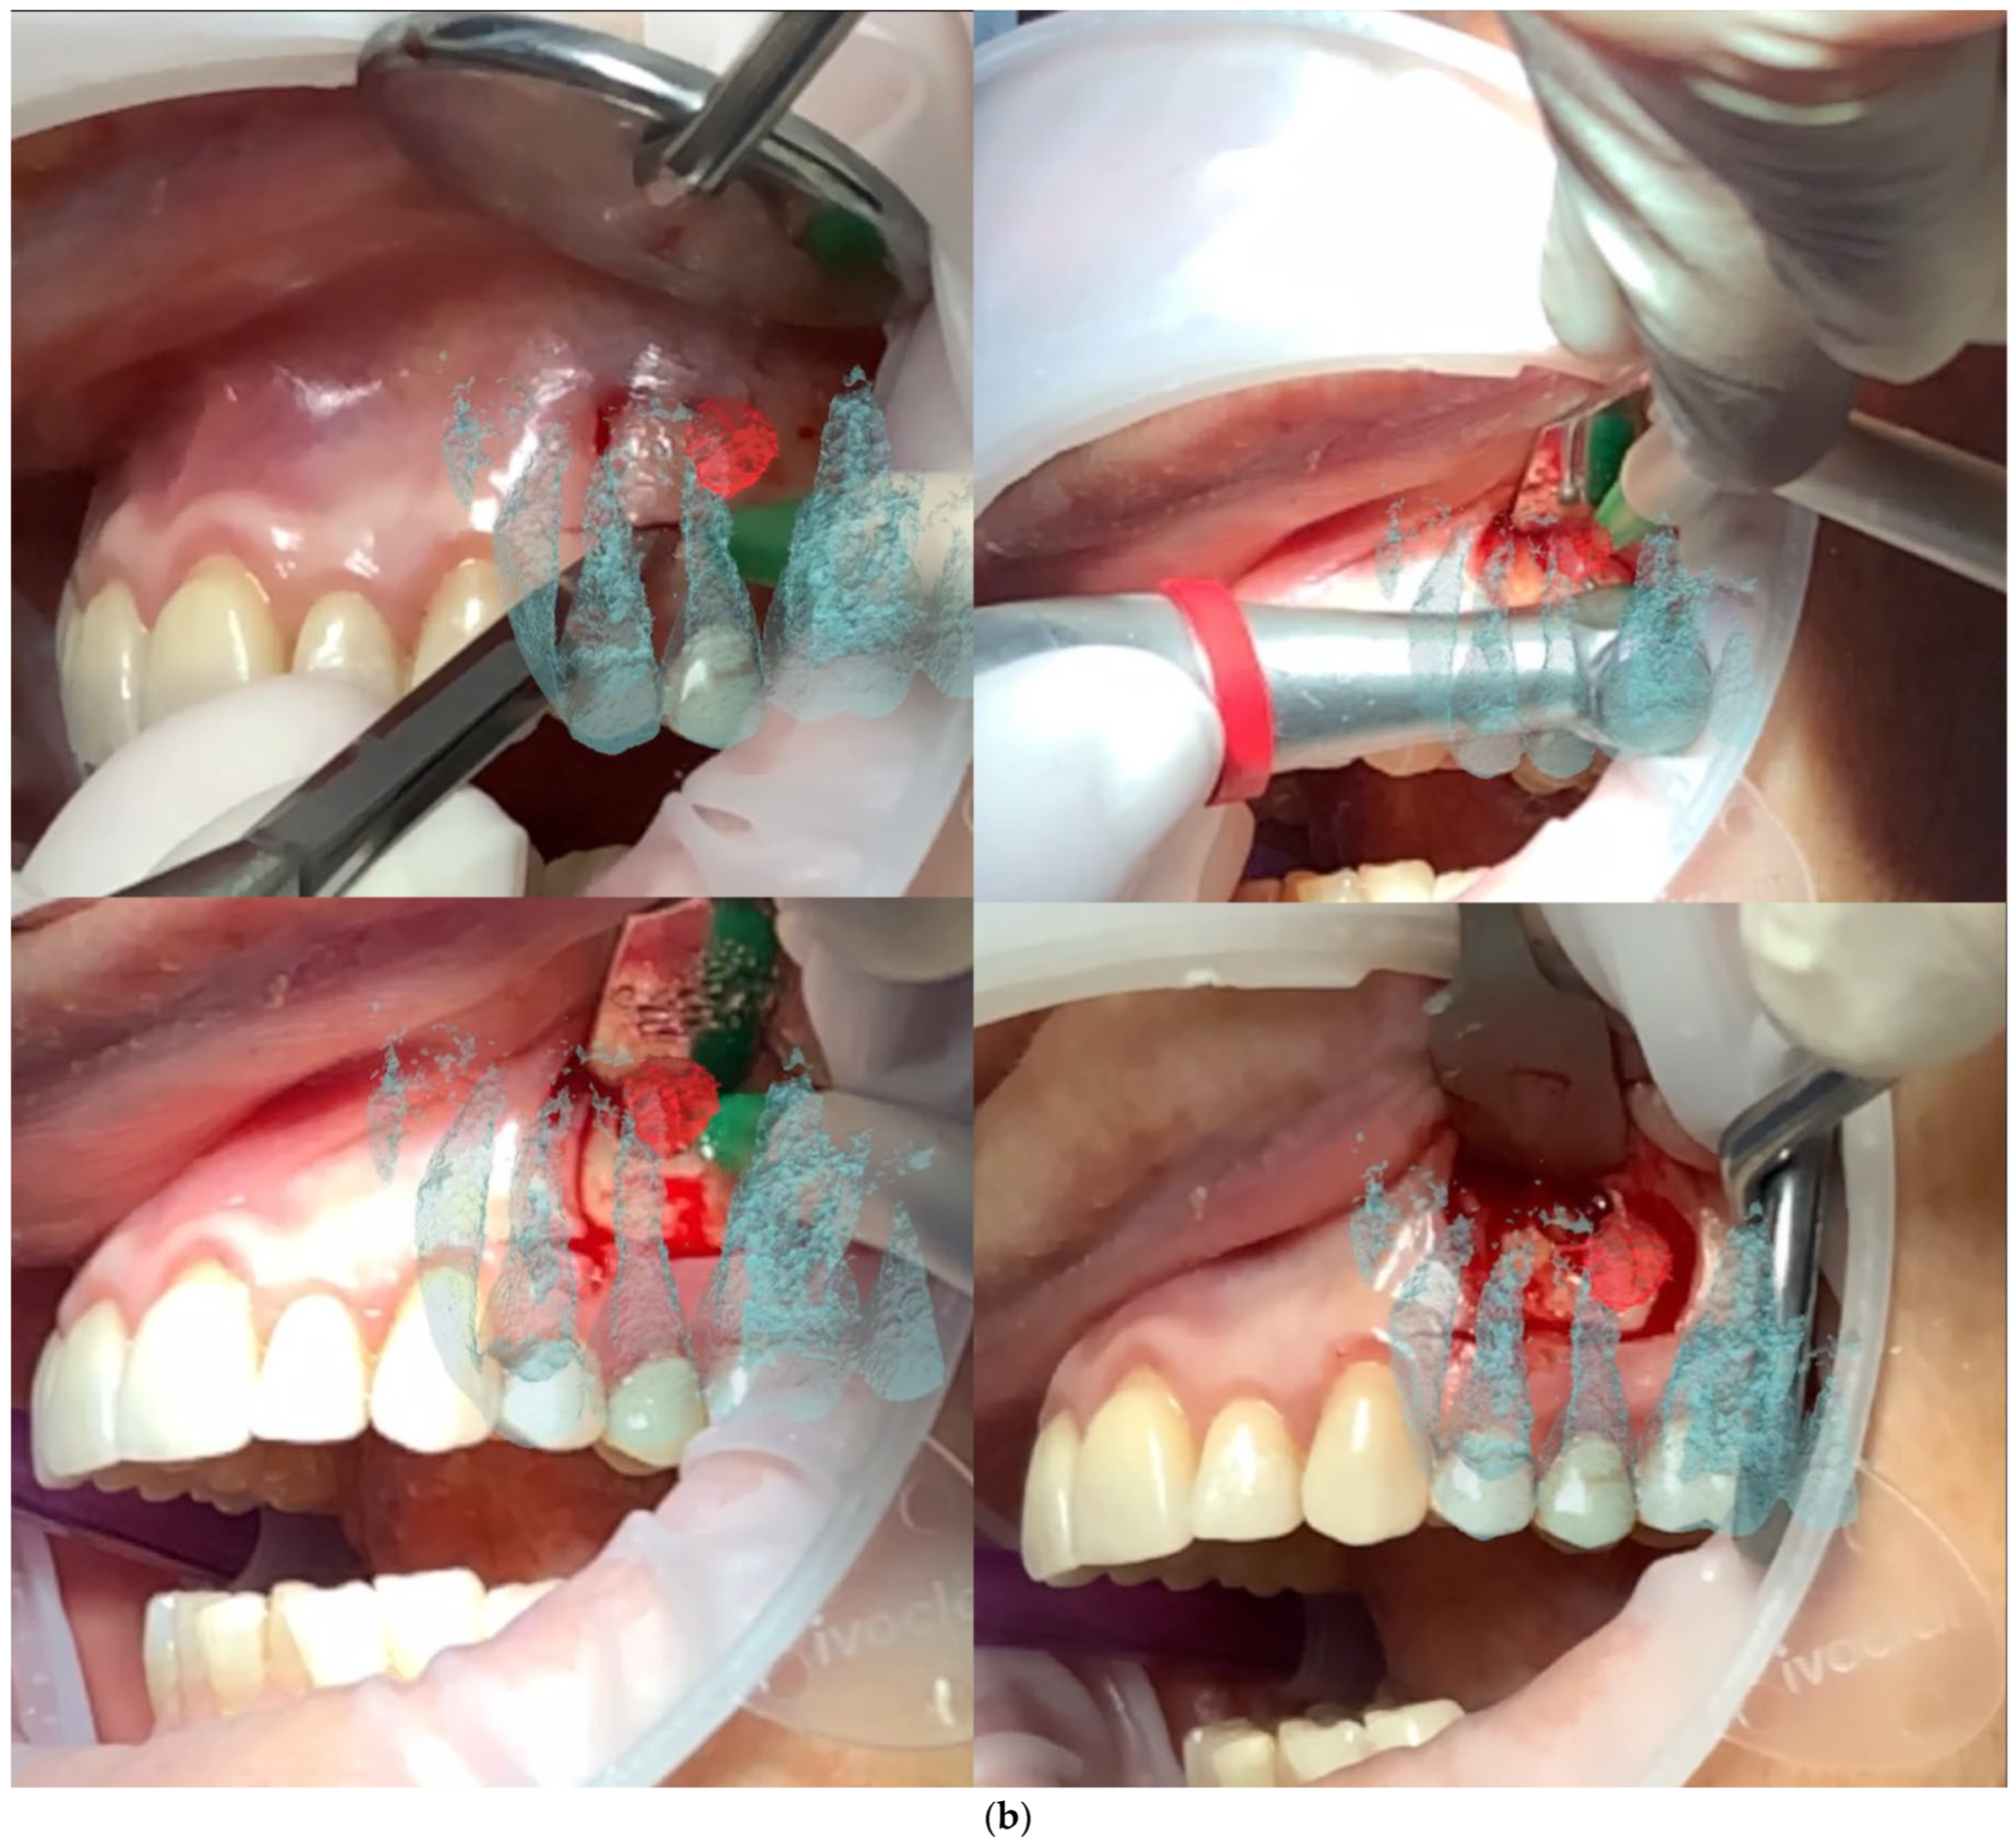

Figure 2. Initial raw overlap is adjusted by the operator following the contour of the dental elements previ-ously segmented until satisfactory visual overlap is reached.

The software was installed on an iPad (Pro 11, software 14.3, Apple, Cupertino, CA, USA) portable device, integrated with dual-camera systems and a LiDAR scanner for real-time precise mapping. By moving the device around the patient’s face, the operator allowed the software to anchor a series of automatically generated points of interest (POIs) to the environment [Figure 1]. Once enough POIs were established, the segmented 3D models were manually aligned with the patient’s visible anatomy and locked in position, maintaining alignment despite device or patient movement [Figure 2]. The operators selected for the overlap of the digital images were previously extensively trained by the creators of the software in 3 different 30 min sessions. The training sessions were performed by overlapping 3d lego™ models to their physical pieces. After successful overlap was achieved, 3D-printed versions of the IOS scans were then overlapped.